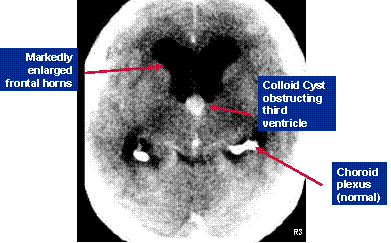

Colloid Cyst of 3

rd

ventricle producing obstructive

hydrocephalus